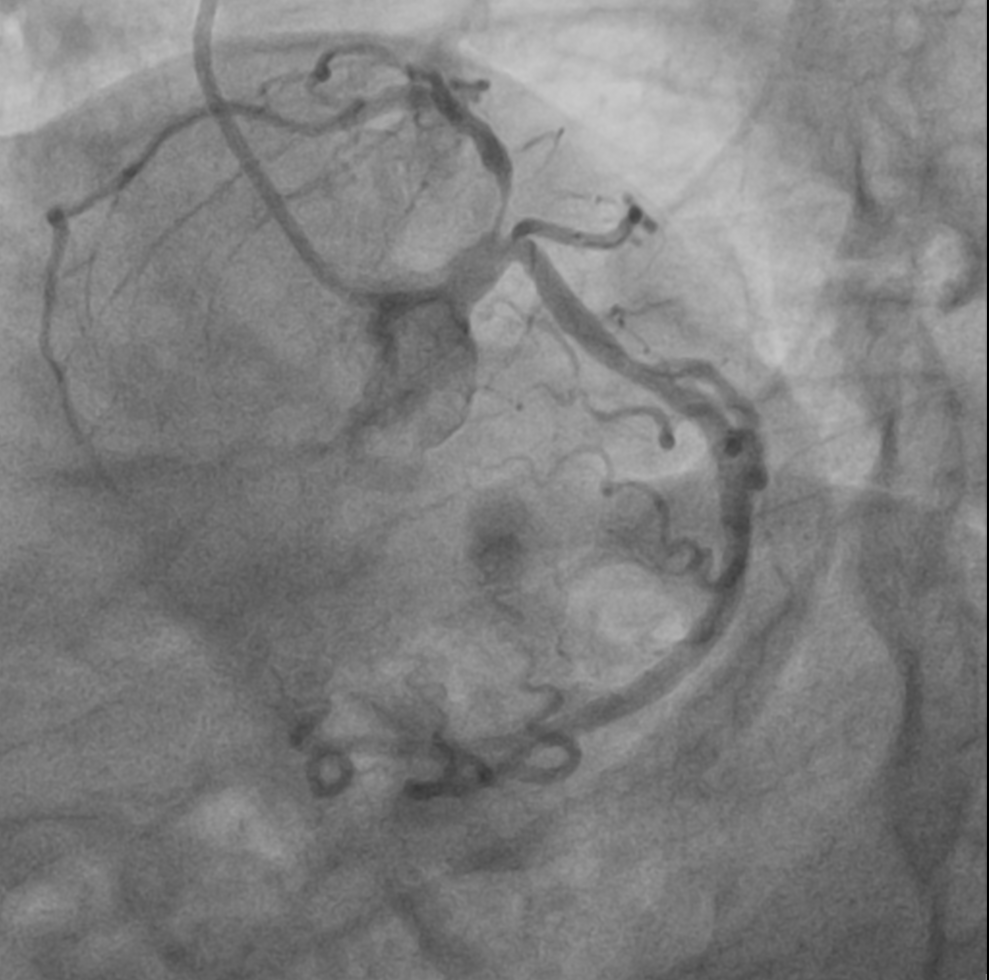

Baseline Coronary Angiography- Angiography was done through right radial artery approach.1. Left coronary angiography : LMCA- distal minor disease, LAD- ostio-proximal 95% long segment disease, LCx-Dominant vessel with minor disease at OM1 ostium.2.Right coronary angiography : Non-dominant vessel.